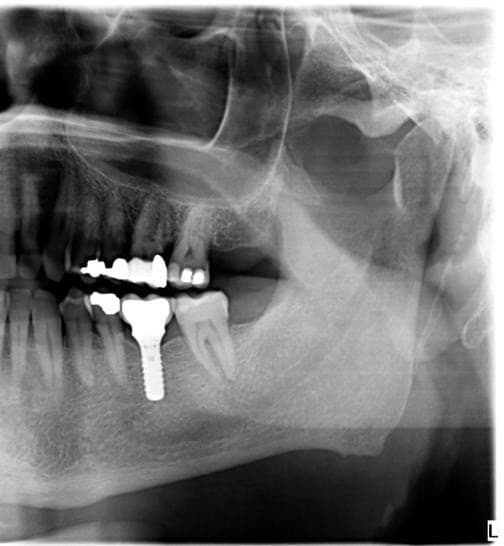

L'implant dentaire est une racine artificielle en titane qui remplace la racine d'une dent manquante. Sur cet implant, une couronne est fixée pour restaurer votre sourire et votre fonction masticatoire.

Qualité Straumann: notre choix

Nous utilisons exclusivement des implants Straumann, leader mondial d'origine suisse:

- Radiographies de contrôle périodiques